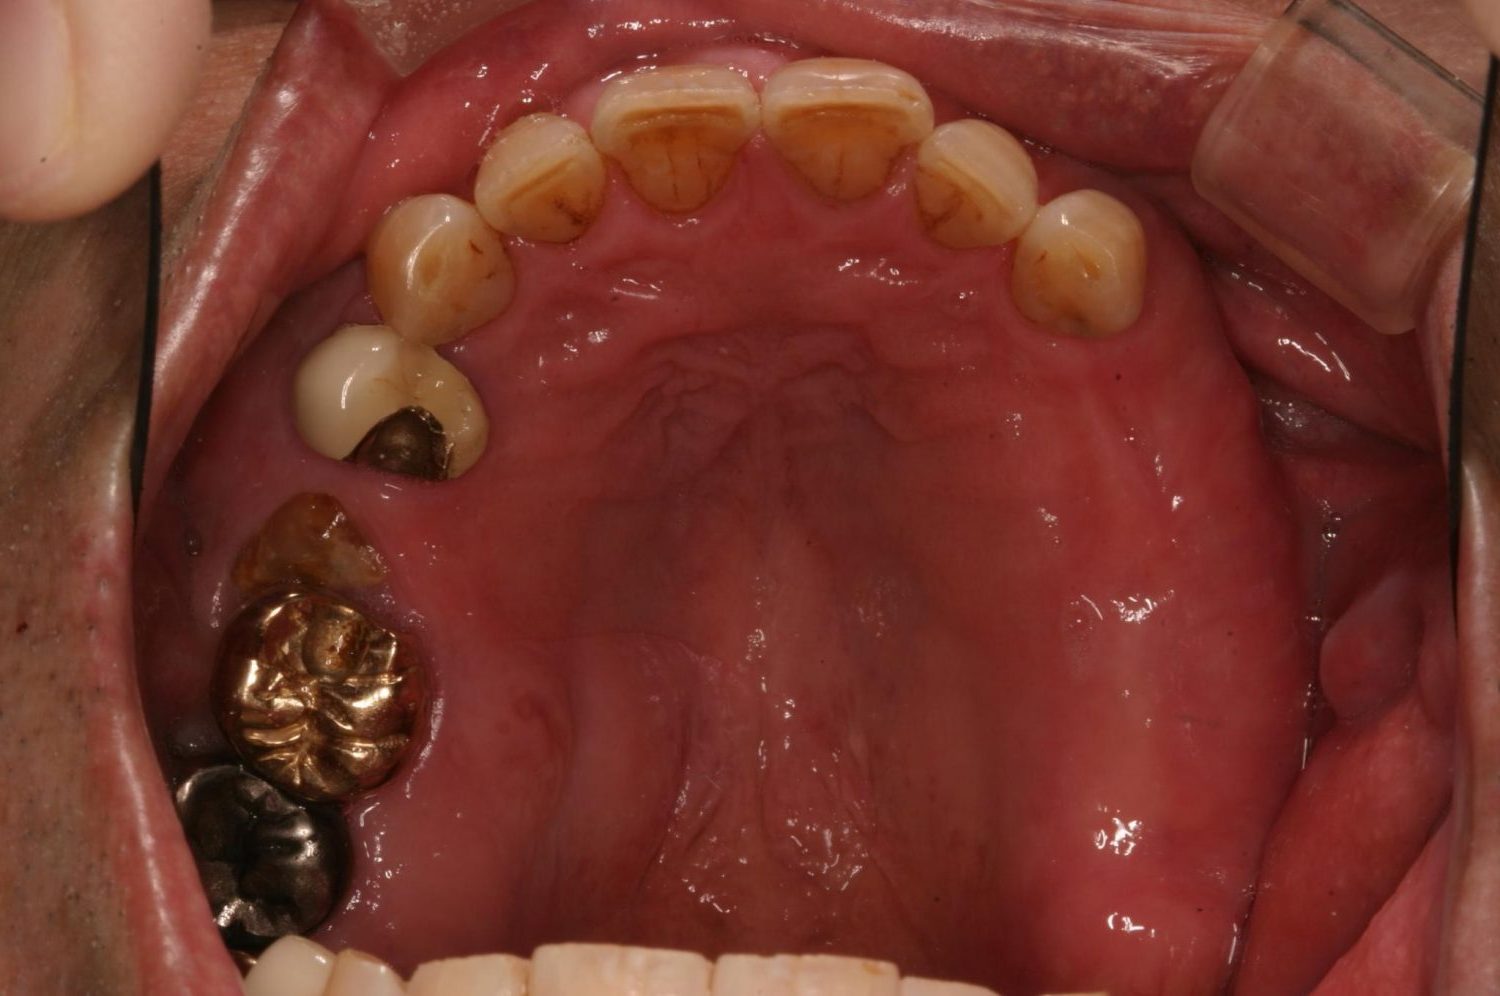

インプラント治療の症例紹介③

Before

After

主訴

むし歯の治療

治療内容

保存不可能な歯の抜歯

下顎にインプラント埋入し咬合再構成

治療費

2,688,400円(税込)

治療期間

14か月

治療回数

21回

想定されたリスク

※上部構造の形態が複雑になるため清掃が難しくなる。インプラント周囲炎の恐れがありました。

多数歯う蝕および多数歯欠損による咬合崩壊、保存不可能な歯の抜歯により上下無歯顎に。下顎に6本インプラント埋入する事で咬合再構成を行った。